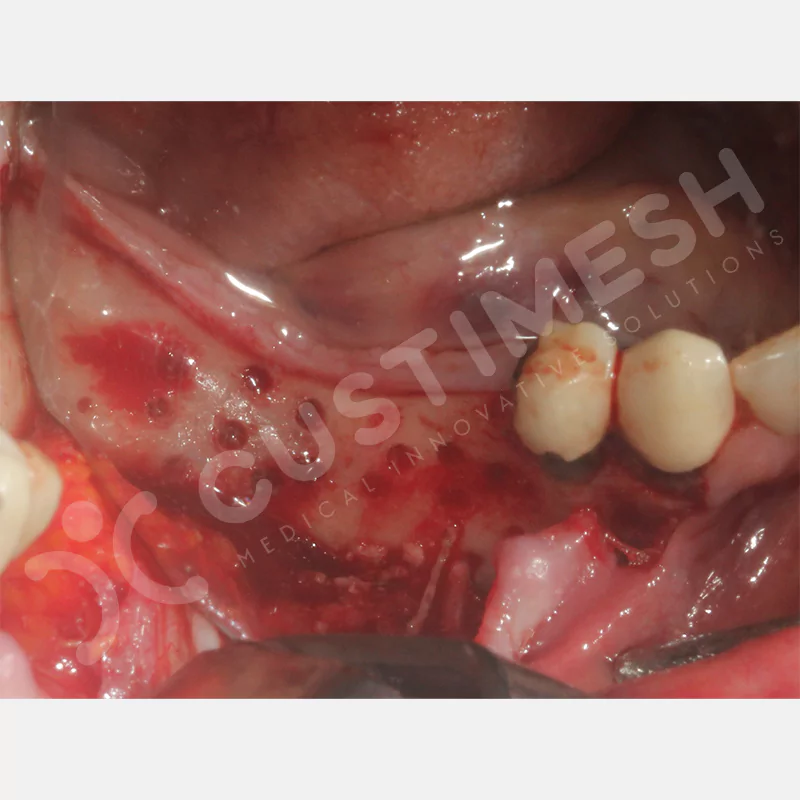

VAKA 1

VAKA 2

VAKA 3